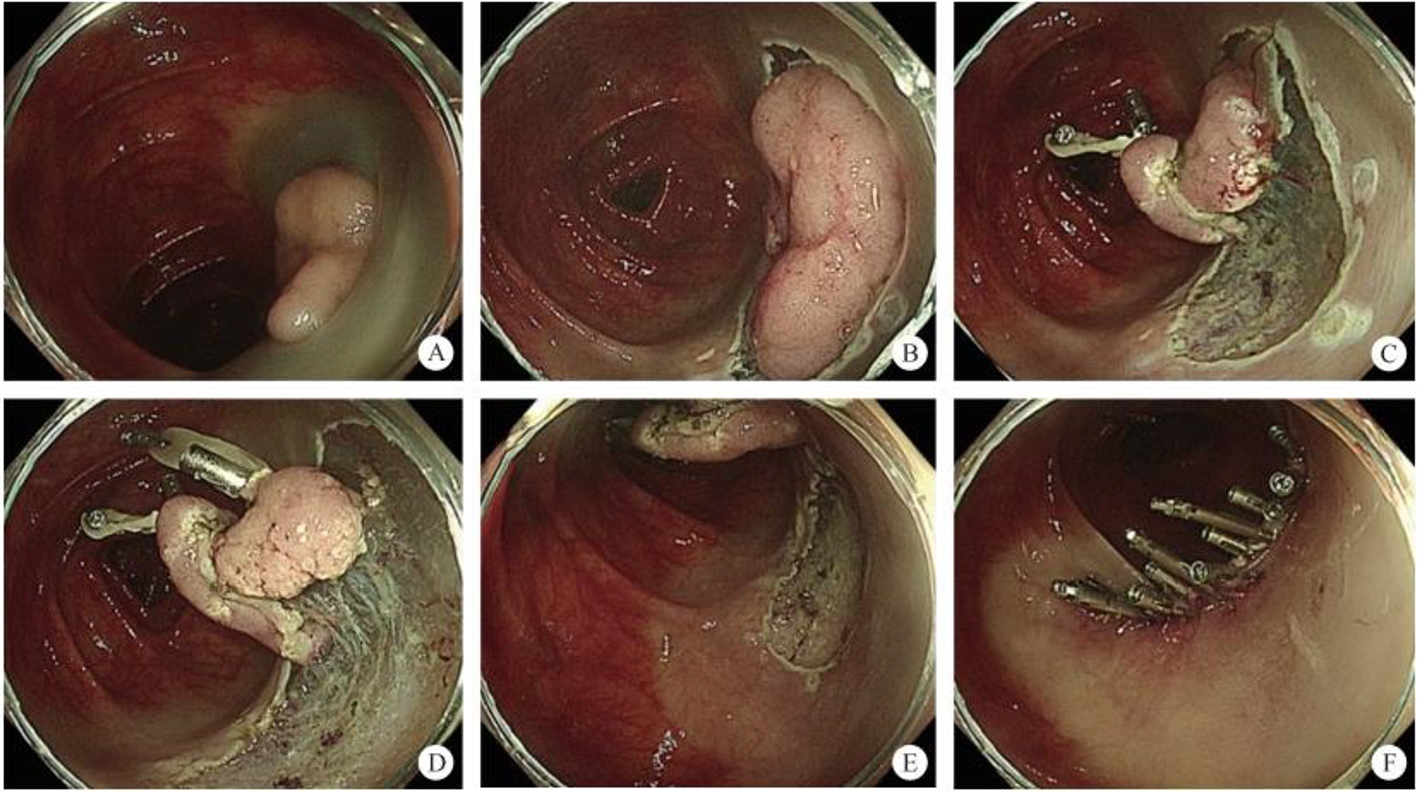

3. Development of the puncture channel. Over the past 10 years, endoscopic ultrasonography (EUS) has gradually become the third eye for endoscopists. Its combination with SMIS brings a new type model for the diagnosis and treatment of organic lesions outside the digestive tubes. For example, EUS-guided bile drainage (EUS–BD) and EUS-guided pancreatic duct drainage (EUS–PD) have been used as effective treatments after the failure of trans-nipple drainage; meanwhile the treatment strategy for acute necrotizing pancreatitis has also changed greatly. EUS-guided super minimally invasive drainage by gastric parietal puncture for pancreatic encapsulated necrosis and EUS-guided pancreatic cystic lesion puncture laurosinol ablation have become the mainstream treatment methods. In the future, SIMS operations like exploring and refining super minimally invasive drainage via a gastric puncture channel for suppurative cholecystitis, EUS-guided super minimally invasive gallstone extraction via a gastric puncture channel, EUS-guided portosystemic shunts and EUS-guided drainage of the chest, the abdomen and pelvic abscess, etc. will be the development directions.

4. Development of the multi-cavity channel. As part of multidisciplinary treatment in the age of precision medicine, combined endoscopic surgery will create chances at sites where the single endoscope does not know what to do, to provide convenience to positions where treatment is difficult. Over the recent 10 years, development of this direction has focused on the endoscopic combined with laparoscopic treatment of upper gastrointestinal stromal tumors and refractory colon polyps. The surgical modes include laparoscopy-assisted endoscopic full-thickness resection (LAFEFR), laparoscopic and endoscopic cooperative surgery (LECS), etc. In the future, developments in this direction will challenge traditional surgical techniques. Endoscopic digestion combined with laparoscopic bi-endoscopic lesion resection + lymph node dissection will further expand the SMIS therapeutic indications in the field of gastrointestinal cancer.